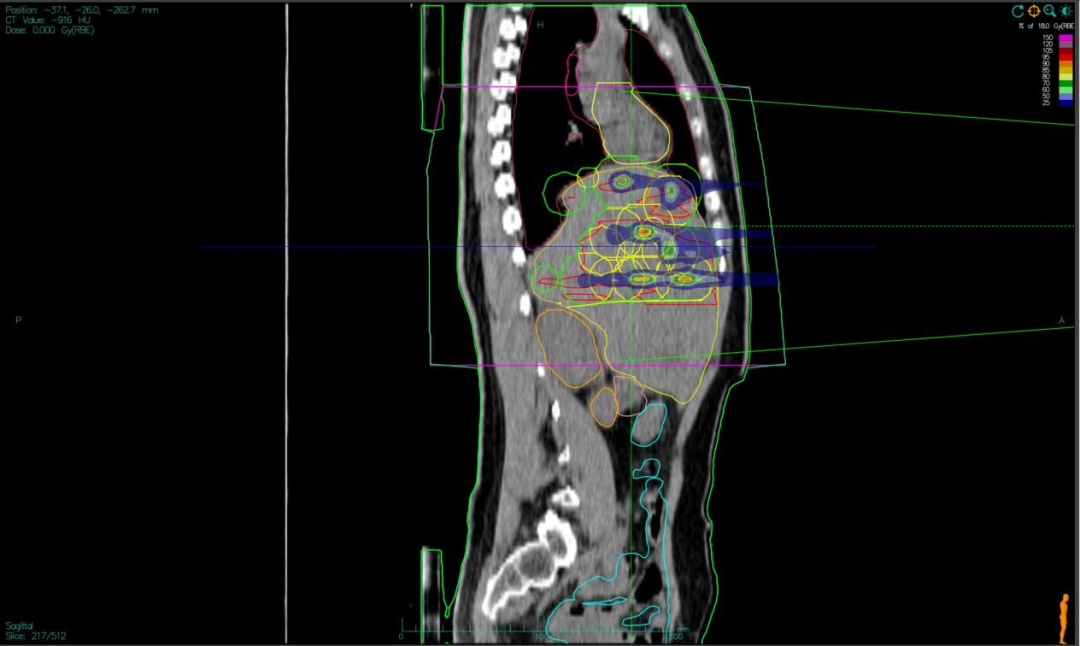

“双布拉格”,并非指代两个物理峰值,而是两大核心治疗理念的深度碰撞与融合。第一个“布拉格”,是物理学范畴的布拉格峰——重离子束流可在体内特定深度释放绝大部分能量,这一特性构筑起“指哪打哪”、极致保护正常组织的物理基石。第二个“布拉格”,是免疫学范畴的布拉格治疗,即国际前沿的PRaG协同治疗方案。它通过精准放疗在局部“点火”,释放肿瘤抗原;以GM-CSF为“导航”,引导免疫系统识别肿瘤细胞;再借助PD-1抑制剂“解除免疫刹车”,让免疫细胞能够持久、全身性地攻击肿瘤,最终追求珍贵的“远隔效应”。而晶格放疗,正是连接两大“布拉格”理念的关键桥梁。针对常规手段无法照射的巨大肿瘤,它将均匀剂量场转化为无数离散的高剂量“能量岛屿”。这种模式不仅能奇迹般保护穿插其中的正常组织与脉管结构,其独特的剂量分布,更被证实可高效诱发免疫原性细胞死亡,将物理打击的能量,转化为激活全身免疫反应的“信号”,让肿瘤的局部治疗与全身控制成为现实。

四大优势协同发力:一,依托重离子射线特有的“布拉格峰”物理特性,实现对深部肿瘤的“定点爆破”;二,采用“晶格放疗”先进布野技术,在巨大肝肿瘤内部精准布设能量“棋盘格”,在高效杀伤肿瘤细胞的同时,为残存正常肝组织与关键脉管留存生存空间;三,将此次精准物理打击,完美嵌入“布拉格治疗”免疫协同策略,以此作为激活全身免疫反应的“点火器”,联合PD-1抑制剂与GM-CSF,力求激发远隔效应,对未被照射的病灶形成攻击;四,引入干细胞支持下的新一代免疫细胞疗法,整合诱导多能干细胞(iPSCs)或间充质干细胞(MSCs)来源的免疫效应细胞(如CAR-T、CAR-NK和TCR-T细胞)与工程化技术,显著提升癌症免疫治疗的可及性与疗效。